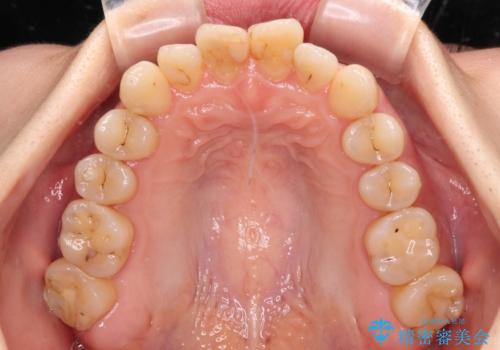

【モニター】開咬を治したい インビザラインによる矯正治療

- 上下前歯の開咬とデコボコを気にして来院された患者様です。

開咬(オープンバイト)はインビザラインによる矯正治療がワイヤー装置と比べて圧倒的に有利であるため、インビザラインによる矯正治療を行うこととしました。

通院されなかった時期があって治療期間が長くなったり、奥歯に抜歯が必要な歯があったりと、治療は一筋縄にはいきませんでしたが、何とか治療を終えることができました。

今後はインプラント治療やむし歯治療を進めて行く予定です。